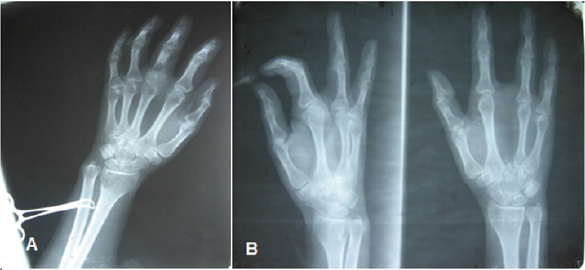

Figure 4: Giant cell tumor located at the level of the proximal epiphysis of the first phalanx of the 3rd finger. B Beam amputation for diagnosis of malignancy.